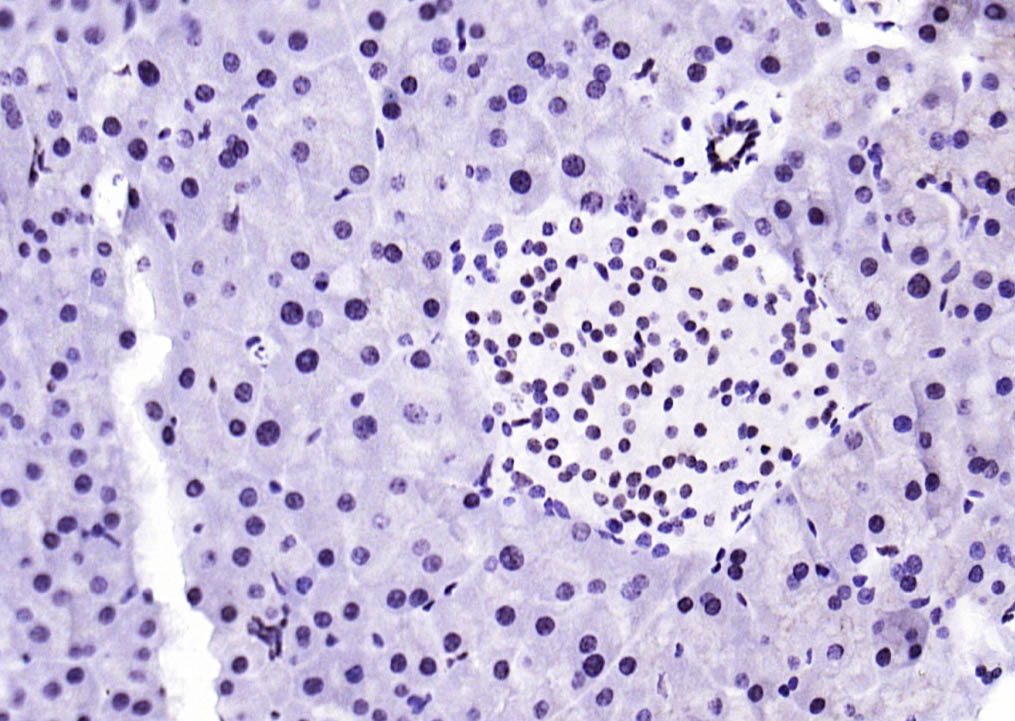

| 产品应用 | WB=1:500-1000, IHC-P=1:50-200, IHC-F=1:50-200, IF=1:50-200 Not yet tested in other applications. |

| {IHC-P} | {1:50-200} |

| {IHC-F} | {1:50-200} |